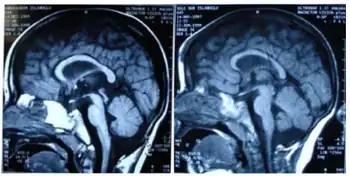

Mothers of infants with this disorder usually have uneventful pregnancies and deliveries, with the child appearing normal and within typical birth weight and length ranges. Infants with GLUT1 deficiency syndrome have a normal head size at birth, but the growth of the brain and skull is slow, in severe cases resulting in an abnormally small head size (microcephaly).[4] Typically, seizures start between one and four months in 90% of cases with abnormal eye movements and apneic episodes preceding the onset of seizures in some cases.[6] Seizures usually are complex to begin with and later become more generalized. Seizure frequency is variable and a history of decreasing frequency during times of ketosis may prompt a diagnosis. It is estimated that 10% of individuals with Glut 1 Deficiency do not have seizures and symptoms are typically less severe in these cases.[7] Most of these non-epileptic cases will still have developmental delay, intellectual delays, and movement disorders such as ataxia, alternating hemiplegia, or dystonia.[7]